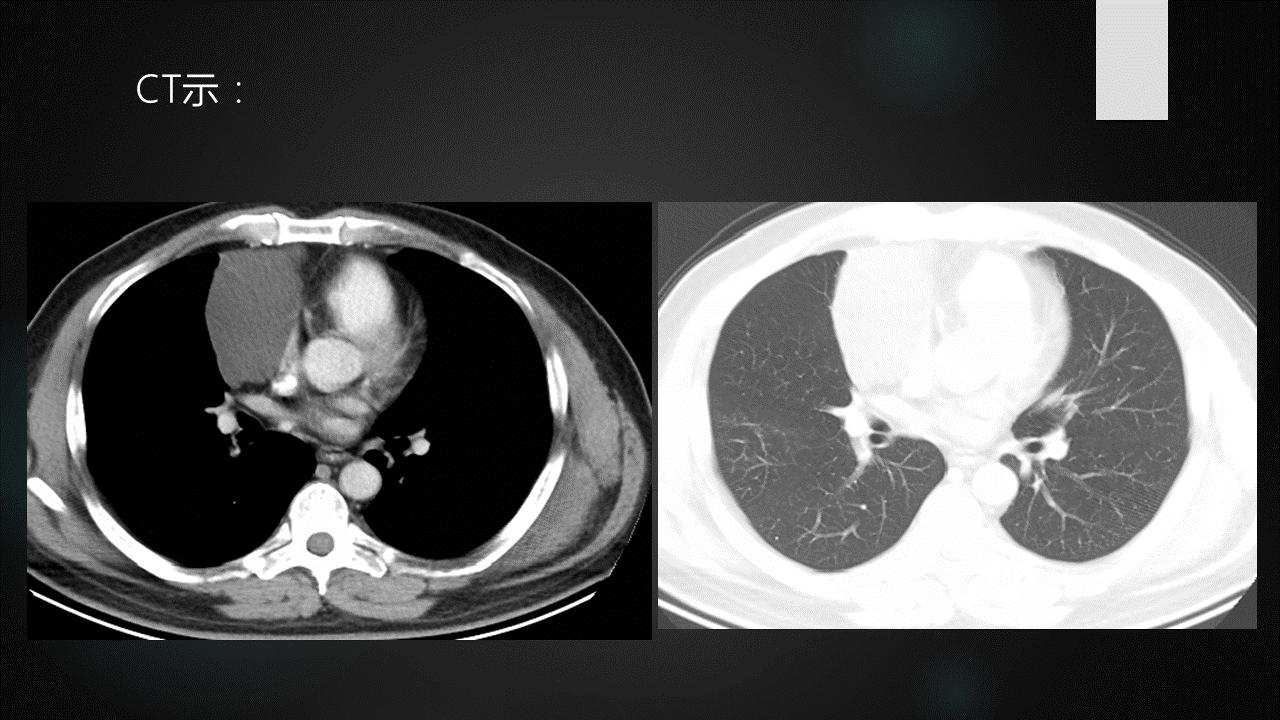

侵袭性胸腺瘤CT图像

a. CT平扫示肺动脉与胸骨间肿块,密度尚均匀,形态不规则b. CT增强示肿块不均匀强化,见低密度囊变区域,肿块与肺动脉之间脂肪间隙消失,肺动脉壁模糊。